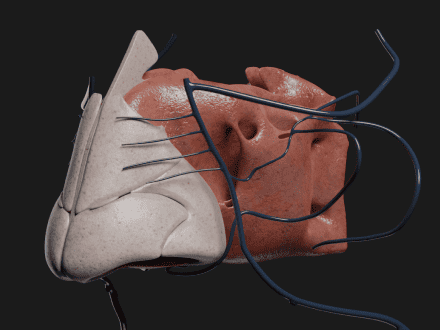

Kirurgi

Muliggjør risikofri preoperativ planlegging og AR-veiledning i sanntid på operasjonsstuen, noe som gir bedre presisjon og pasientsikkerhet.